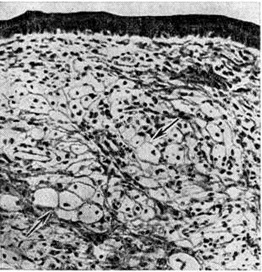

Ксантома (xanthoma; греческий хапthos золотисто-жёлтый + -oma; синонимы: сальный моллюск, липоматозная фиброма) — очаговое отложение в коже и некоторых тканях триглицеридов и холестерина, вызванное нарушениями жирового обмена. Термин «ксантома» введён в 1864 год Смитом (W. F. Smith). Морфологически основой Ксантома являются так называемый ксантомные клетки (рис.) — одно или многоядерные фагоциты с пенистой цитоплазмой, содержащей двоякопреломляющие жировые включения; в дерме может быть лимфогистиоцитарная инфильтрация, встречаются гигантские клетки инородных тел, прогрессирует фиброз.

Рис

Микропрепарат туберозной ксантомы: стрелками указаны скопления ксантомных клеток.